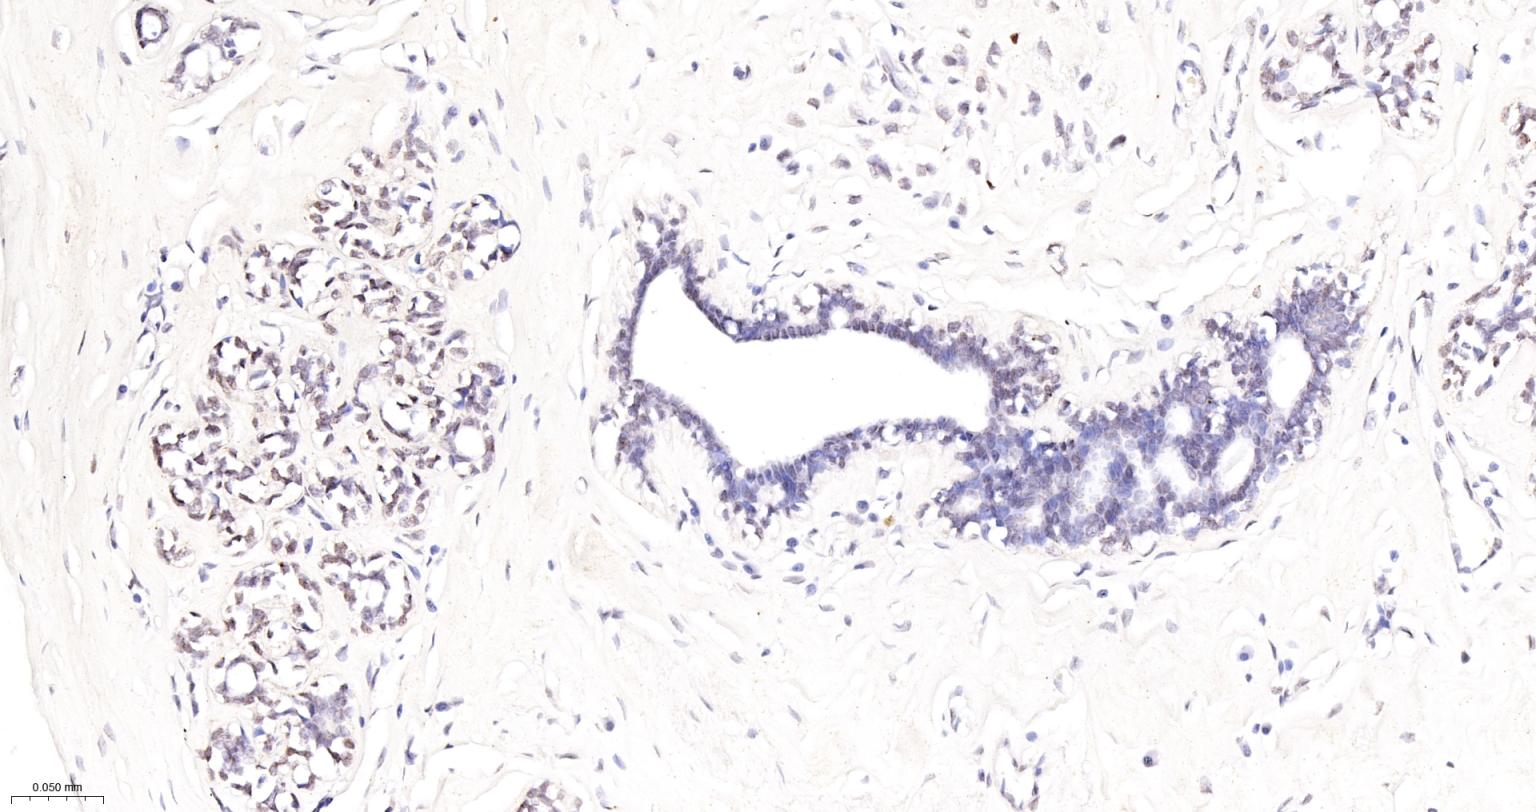

Paraformaldehyde-fixed, paraffin embedded Human Breast Cancer; Antigen retrieval by boiling in sodium citrate buffer (pH6.0) for 15 min; The section was incubated with phospho-DNA PKcs (S2056) Monoclonal Antibody, Unconjugated (bsm-63104R) at 1:200 overnight at 4°C, followed by conjugation to the bs-0295G-HRP and DAB (C-0010) staining.